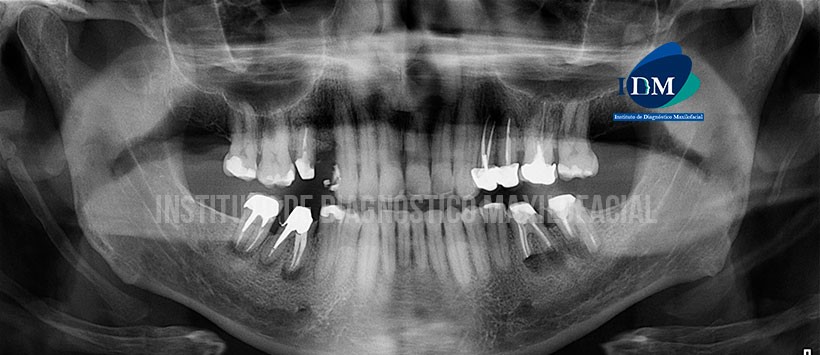

Paciente de sexo masculino de 54 años acude al Instituto de Diagnóstico Maxilofacial para evaluación del sector dentario posterior.

A la evaluación de la radiografía panorámica se aprecia una mineralización de ambos procesos estilohioideos, neumatización alveolar de ambos senos maxilares, ausencia de piezas dentarias (18, 28, 38, 48 y 14), múltiples restauraciones, múltiples piezas con material de obturación de conductos y espigos protésicos con sus respectivas restauraciones y coronas protésicas. Siendo lo mas resaltante los proceso osteolíticos en zona apical de las piezas 36, 37, 47 y 46 así como el aumento de la densidad óseas circundante (Osteítis). (Figura 1)